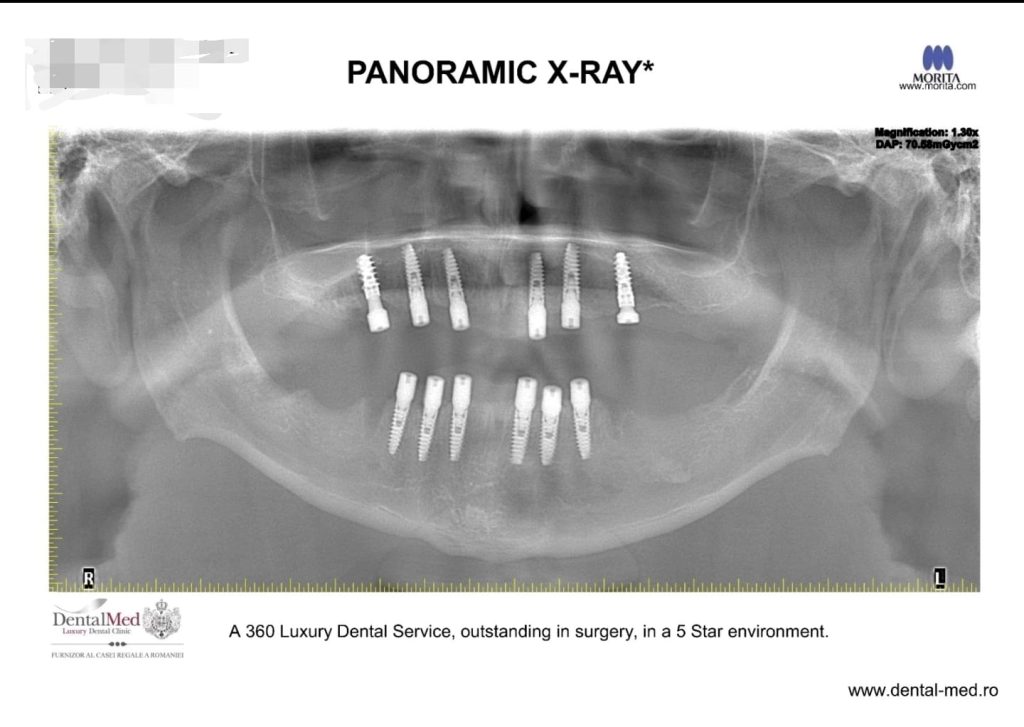

- Consultația inițială și evaluarea imagistică – Medicul realizează o examinare clinică și radiologică (radiografie panoramică, tomografie computerizată) pentru a stabili dacă osul are structura necesară pentru susținerea implantului.

12 proceduri de implant dentar

14 extractii dentare

Aditii osoase

Sedare intravenoasa (i.v.sedation)

——-‐‐———–

One Stage Surgery

Timp total 1h 40 minute

Succesul unei proceduri de implant dentar începe cu o etapă riguroasă de evaluare și planificare. În cadrul Clinicii DentalMed Luxury, pacientul beneficiază de o examinare radiologică completă, ce include RX panoramic și tomografie computerizată (CT). Aceste investigații sunt realizate in-house, folosind tehnologia de top MORITA – lider mondial în imagistică dentară – ceea ce asigură precizie maximă și rapiditate în obținerea rezultatelor.

Cu ajutorul imaginilor tridimensionale detaliate, echipa medicală poate evalua cu acuratețe structura osoasă, poziția dinților și eventualele complicații ascunse. Pe baza acestor informații, se stabilește un plan de tratament personalizat, adaptat nevoilor specifice ale fiecărui pacient, pentru a asigura succesul intervenției și rezultate pe termen lung.